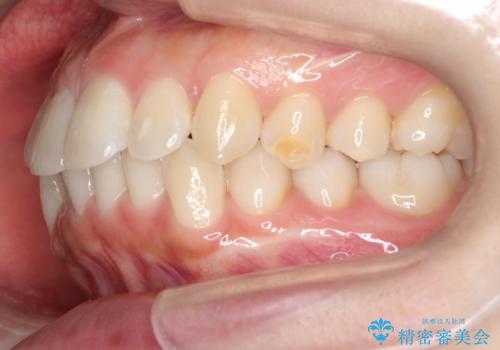

- 口元をさげたいという主訴で来院されました。4番の歯を4本抜歯し、審美装置にて治療をしました。

抜歯をしたことで口元の突出感が改善しました。約2年を予定していた矯正ですが、約1年という短い期間で終了できました。